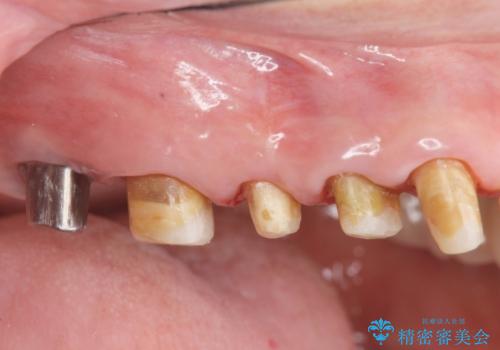

見た目の悪いクラウンをやりかえたい

- 色や形、適合の悪いクラウンの再治療を希望され来院されました。

装着されているクラウンを除去し、自然な色調のジルコニアクラウンによる審美生の改善、インプラントを用いた欠損部の機能回復を計画します。